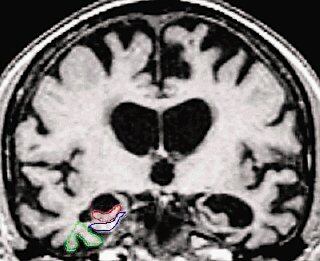

El Alzheimer y otras enfermedades que causan demencia en adultos mayores podrán ser diagnosticadas en vida mediante imágenes por resonancia magnética (MRI en inglés).

Los científicos desarrollaron un procedimiento llamado Índice Estructural de Anomalías (STAND-Map, por sus siglas en inglés), que consiste en analizar las imágenes por resonancia magnética de los pacientes y hacer predicciones del diagnóstico de estas enfermedades a partir de las zonas estructurales del cerebro en donde se desarrollan. Al utilizar el STAND-Map durante el estudio se obtuvo un 80% de predicciones patológicas precisas de estos males.